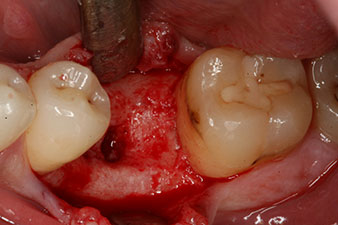

No obstante, seis semanas después de la extracción, tras la disección del colgajo mucoperióstico, se observó una osificación incompleta en el área del antiguo alvéolo mesial.

Tras la extirpación minuciosa del tejido de granulación, se incorporó el implante tal como se había planificado (blueSky, bredent).

Este habría permitido una cicatrización abierta o incluso un tratamiento inmediato. Sin embargo, como no se disponía de suficiente hueso en la parte crestal del implante, el área se aumentó con las virutas óseas recopiladas durante la preparación del lecho del implante y se suturó para que no penetrara saliva.